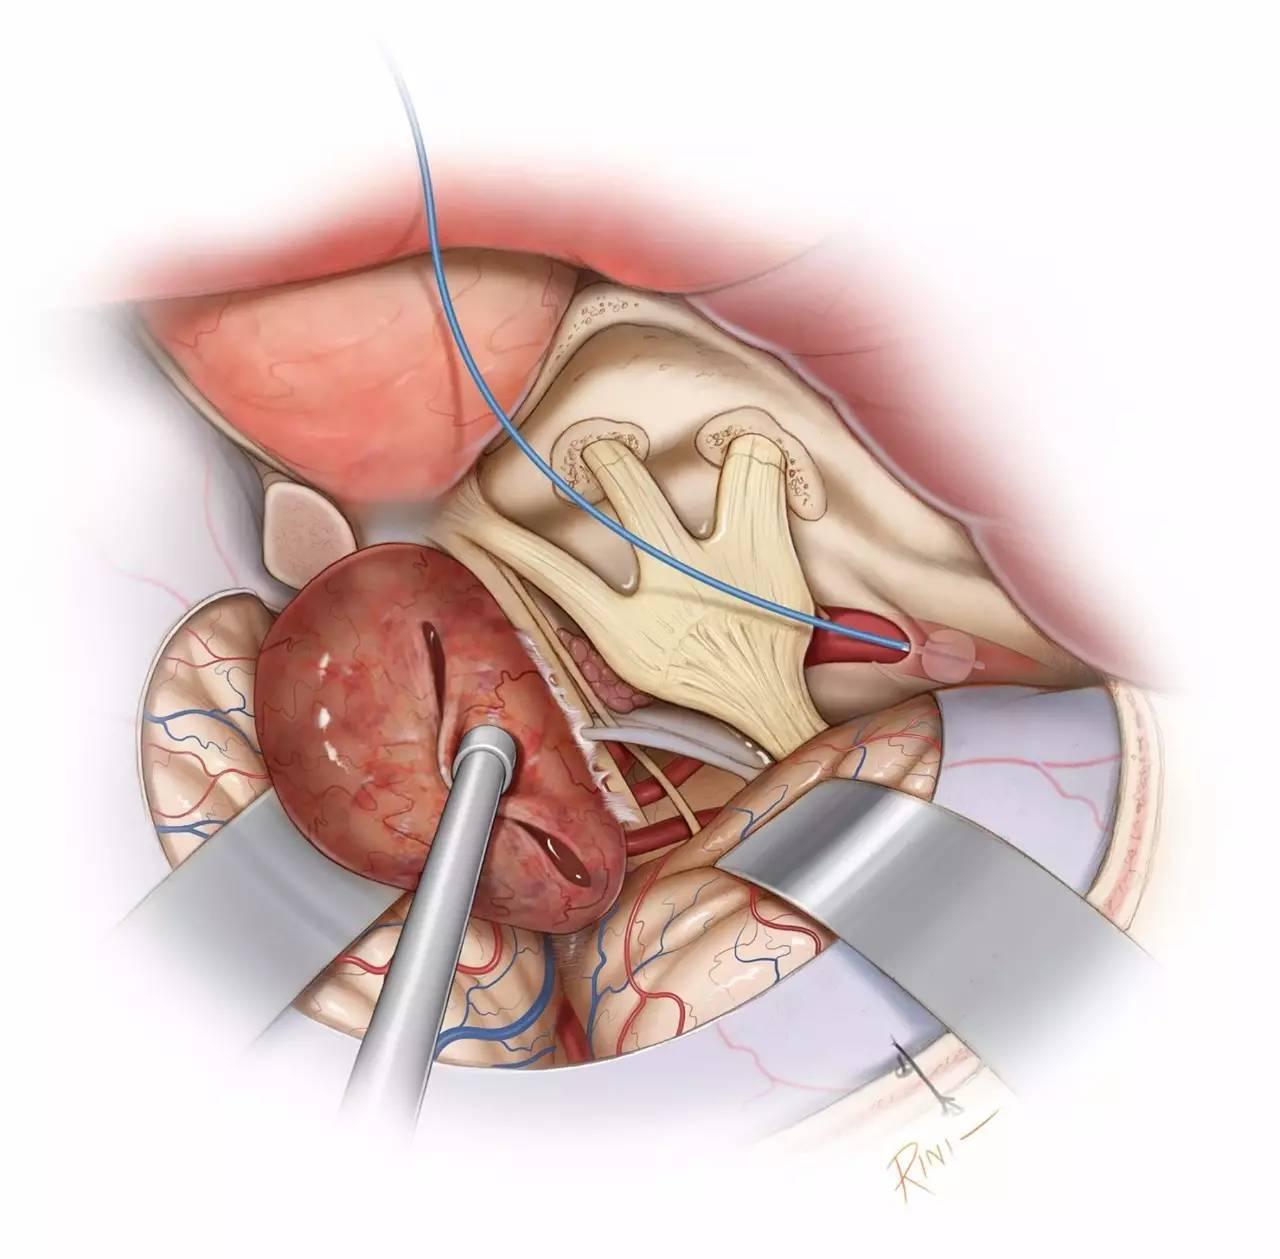

图8:对海绵窦周围区域的暴露,可通过眶颧开颅或扩大翼点开颅,结合硬膜外前床突切除术即眶后部切开术来实现。对于硬膜内入路,首先切除肿瘤的窦外部分,并在早期切开镰状韧带实现视神经减压。可沿蝶骨翼内侧的硬膜去除肿瘤窦外部分的血供。开放三叉神经出颅的骨孔,可暴露侵入这些骨孔的肿瘤。

图9:先处理累及视神经的肿瘤,以免在之后的操作中损伤视神经。将肿瘤包膜从视神经上锐性剥离下来。注意保护神经下表面的穿通动脉。注意处理肿瘤基底以减少血供,并尽可能彻底的瘤内减压。使用固定牵开器适当牵开额叶和颞叶以对其进行保护。

图10:继续将肿瘤包膜与视神经颈内动脉池内各神经血管结构相分离。该阶段最容易损伤的神经为滑车神经,可于天幕游离缘辨认并追踪其入海绵窦内。紧密粘连于神经的肿瘤碎片,应避免强行切除,以保留神经功能。穿通动脉也应予以保护。

图11:将肿瘤从半月神经节上仔细分离。在保证安全的前提下,切除侵入三叉神经各骨孔内的肿瘤,必要时可扩大这些骨孔。

图12:切除肿瘤后最终的术野。滑车神经周围残留少量肿瘤,以避免永久性神经功能障碍。